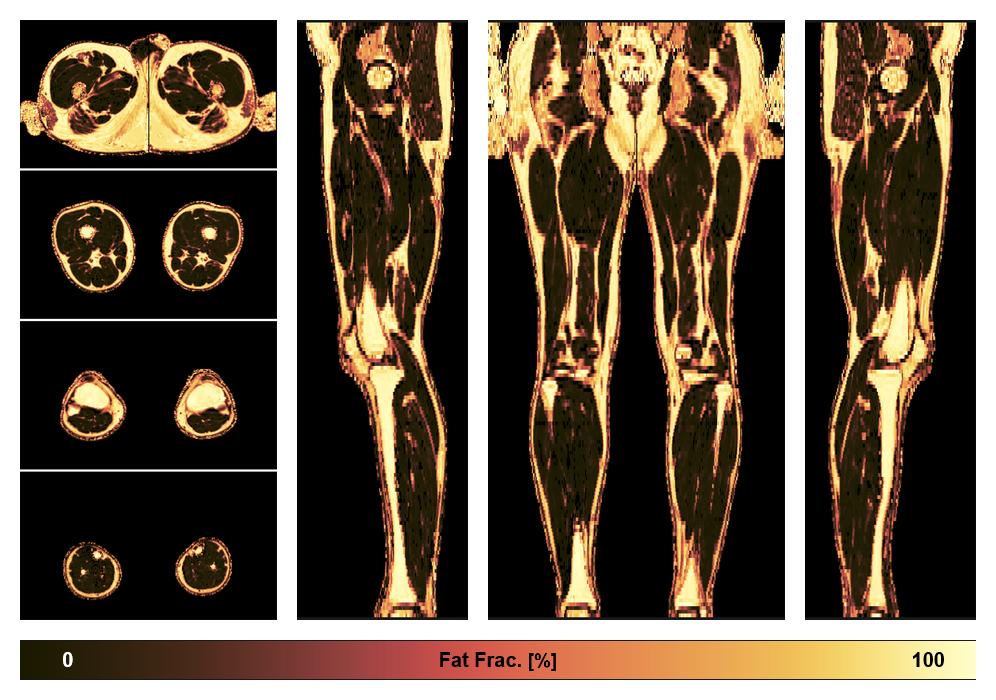

• Fat fraction

The fat fraction of the lower extremity obtained from the dixon reconstruction for muscle water fat quantification.